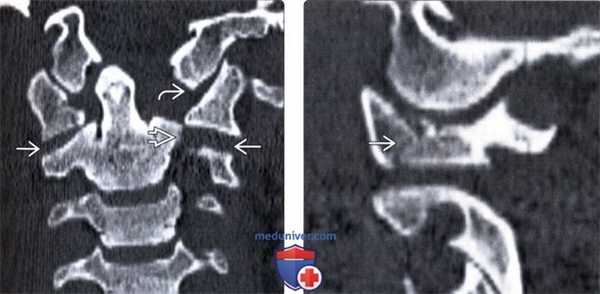

(Слева) КТ, фронтальный срез: латеральная дислокация боковой массы С1. Верхушка зубовидного отростка находится у края большого затылочного отверстия в связи с потерей высоты атланта. Обратите внимание на повреждение атланто-затылочного сустава и вывих в дугоотростчатом суставе С1-С2. Также здесь имеет место перелом левой суставной колонны С2.

(Справа) КТ, сагиттальный срез: часть взрывного перелома С1, линия которого проходит через боковую массу позвонка, подчеркивая роль аксиальной нагрузки со стороны мыщелка затылочной кости в механизме возникновения данного повреждения.